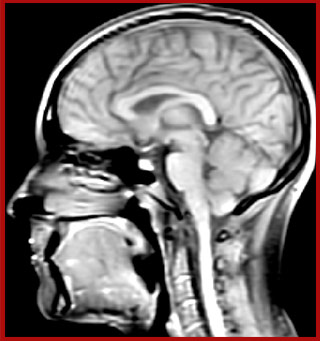

Multiple sclerosis or MS is a neurodegenerative disease that is characterized by myelin degradation, resulting in cognitive and motor deficits. According to Dr. Shannon Kolind, MR imaging for diagnosis and monitoring of MS is moving to higher field strength and using more 3D sequences, as reflected in the CMSC guidelines [1-3].

At UBC, a lot of the MS-related work focuses on myelin imaging. “We're born with very little myelin and that increases as the brain grows, which is important for nerve signal propagation. Multiple sclerosis on the other hand, degenerates the myelin with the opposite effect. So, myelin has a really important role in brain function, and having a tool that measures myelin can be extremely useful, we feel,” says Dr. MacKay.

Myelin water imaging (MWI) is a breakthrough technique that was pioneered at UBC for measuring myelin content in the brain, in vivo. “Because the T2 time of water in myelin is much shorter than the T2 of water in the intraand extracellular spaces, we can separate out the myelin water signal.”

Dr. Rauscher says, “For MWI we perform 3D T2 with 32 or more echoes. This used to take a long time, but with Compressed SENSE we can decrease this to ten minutes for the whole head. Because of the large field of view (FOV) on the readout direction, we even get information from the brainstem, which we previously missed when we were using the GRASE approach. Having the whole head scan is nice because it has spatial resolution, orientation and FOV that are comparable to the standard 3D clinical MS scans, including the FLAIR and 3D T2, and a 3D T1 for brain volume.”

T1 - Weighted, Myelin Water Fraction Superimposed

MWI Spinal cord coverage

Spinal cord coverage

MWI Smaller, more isotropic voxels

Smaller, more isotropic voxels

MWI Excellent detail in quantitative maps

Excellent detail in quantitative maps

Images courtesy of Adam Dvorak, Department of Physics and Astronomy, University of British Columbia

20%

Myelin water fraction

0%